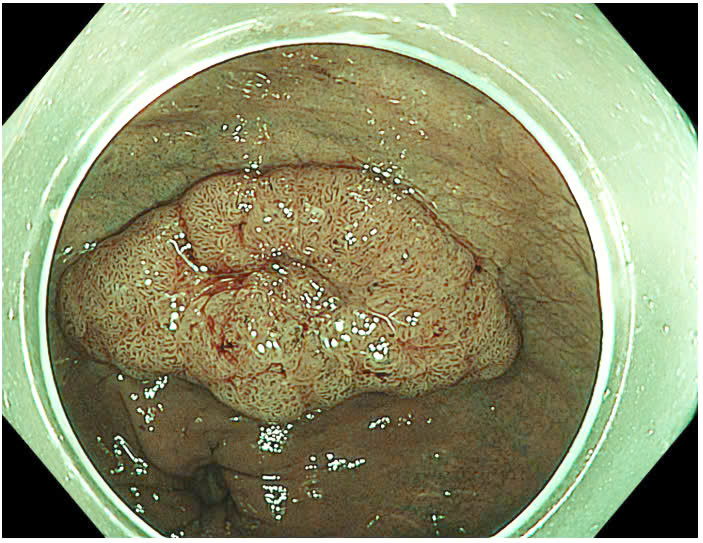

Qua nội soi, các bác sĩ phát hiện một polyp dẹt lớn ở trực tràng có kích thước từ #25-30 mm, với phân loại JNET 2A-2B. Đây là dạng polyp có nguy cơ phát triển thành ung thư cao nếu không được xử lý kịp thời. Bệnh nhân có kết quả giải phẫu bệnh (GPB) kết luận polyp có nghịch sản độ thấp của tuyến đại tràng, tức là ung thư giai đoạn sớm, chưa xâm lấn nhưng có tiềm năng phát triển thành ung thư xâm lấn nếu không điều trị kịp thời.

Bệnh nhân đã được chỉ định thực hiện phương pháp Nội soi cắt tách dưới niêm mạc (ESD), một kỹ thuật tiên tiến để điều trị ung thư sớm. Thủ thuật được thực hiện nhằm loại bỏ hoàn toàn polyp lớn và vùng mô bị tổn thương K sớm.